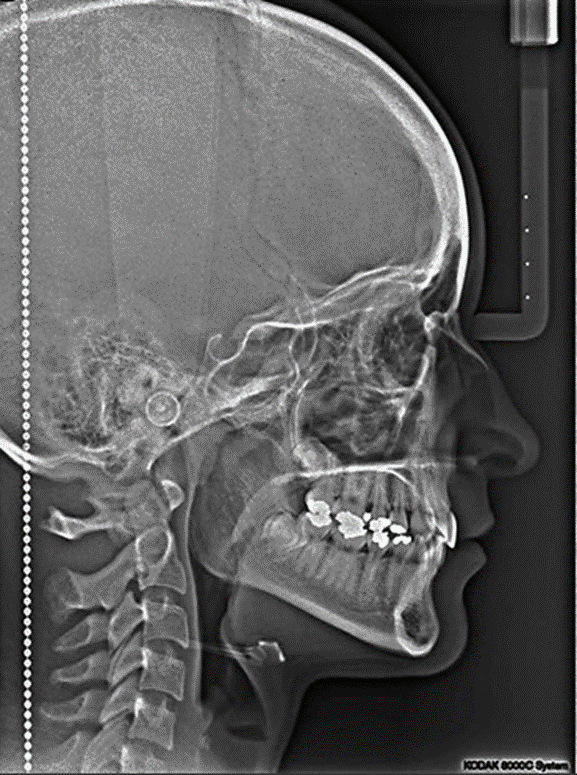

Radiografía Lateral de Cráneo

Muestra los huesos de la cara y el cráneo junto con el perfil

de tejidos blandos de la cara proporcionara información muy general de la cara,

cráneo y columna cervical.

1.- Sutura Lambdoidea

2.- Pterion

3.- Bregma

4.- Conducto auditivo

5.- Lamina Basilar

6.- Apófisis clinoides posterior

7.- Apófisis clinoidea anterior

8.- Silla Turca

9.- Atlas

10.- Axis

11.- Mandíbula o maxilar inferior

12.- Seno esfenoidal

13.- Seno frontal

14.- Seno Maxilar

15.- Protuberancia occipital int.

Usos en especialidades:

*Los ortodontistas ocupan esta

técnica para evaluar el crecimiento facial